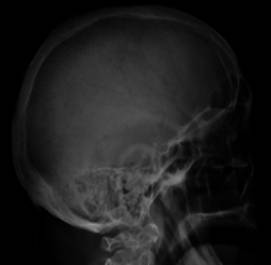

Simple

radiography is indicated for the evaluation of skeleton lesions, and a skeletal

survey is performed when myeloma is in the differential diagnosis. Plain

radiography remains the gold standard imaging procedure for staging newly

Perform a

complete skeletal series at diagnosis of MM, including the skull (a very common

site of bone lesions in persons with MM), the long bones and the spine.

Onventional

plain radiography can usually depict lytic lesions. Such lesions appear as

multiple, rounded, punched-out areas found in the skull, vertebral column,

ribs, and/or pelvis. Less common but not rare sites of involvement include the

Fig. 1. Skull X-ray showing multiple

lucencies due to multiple myeloma.